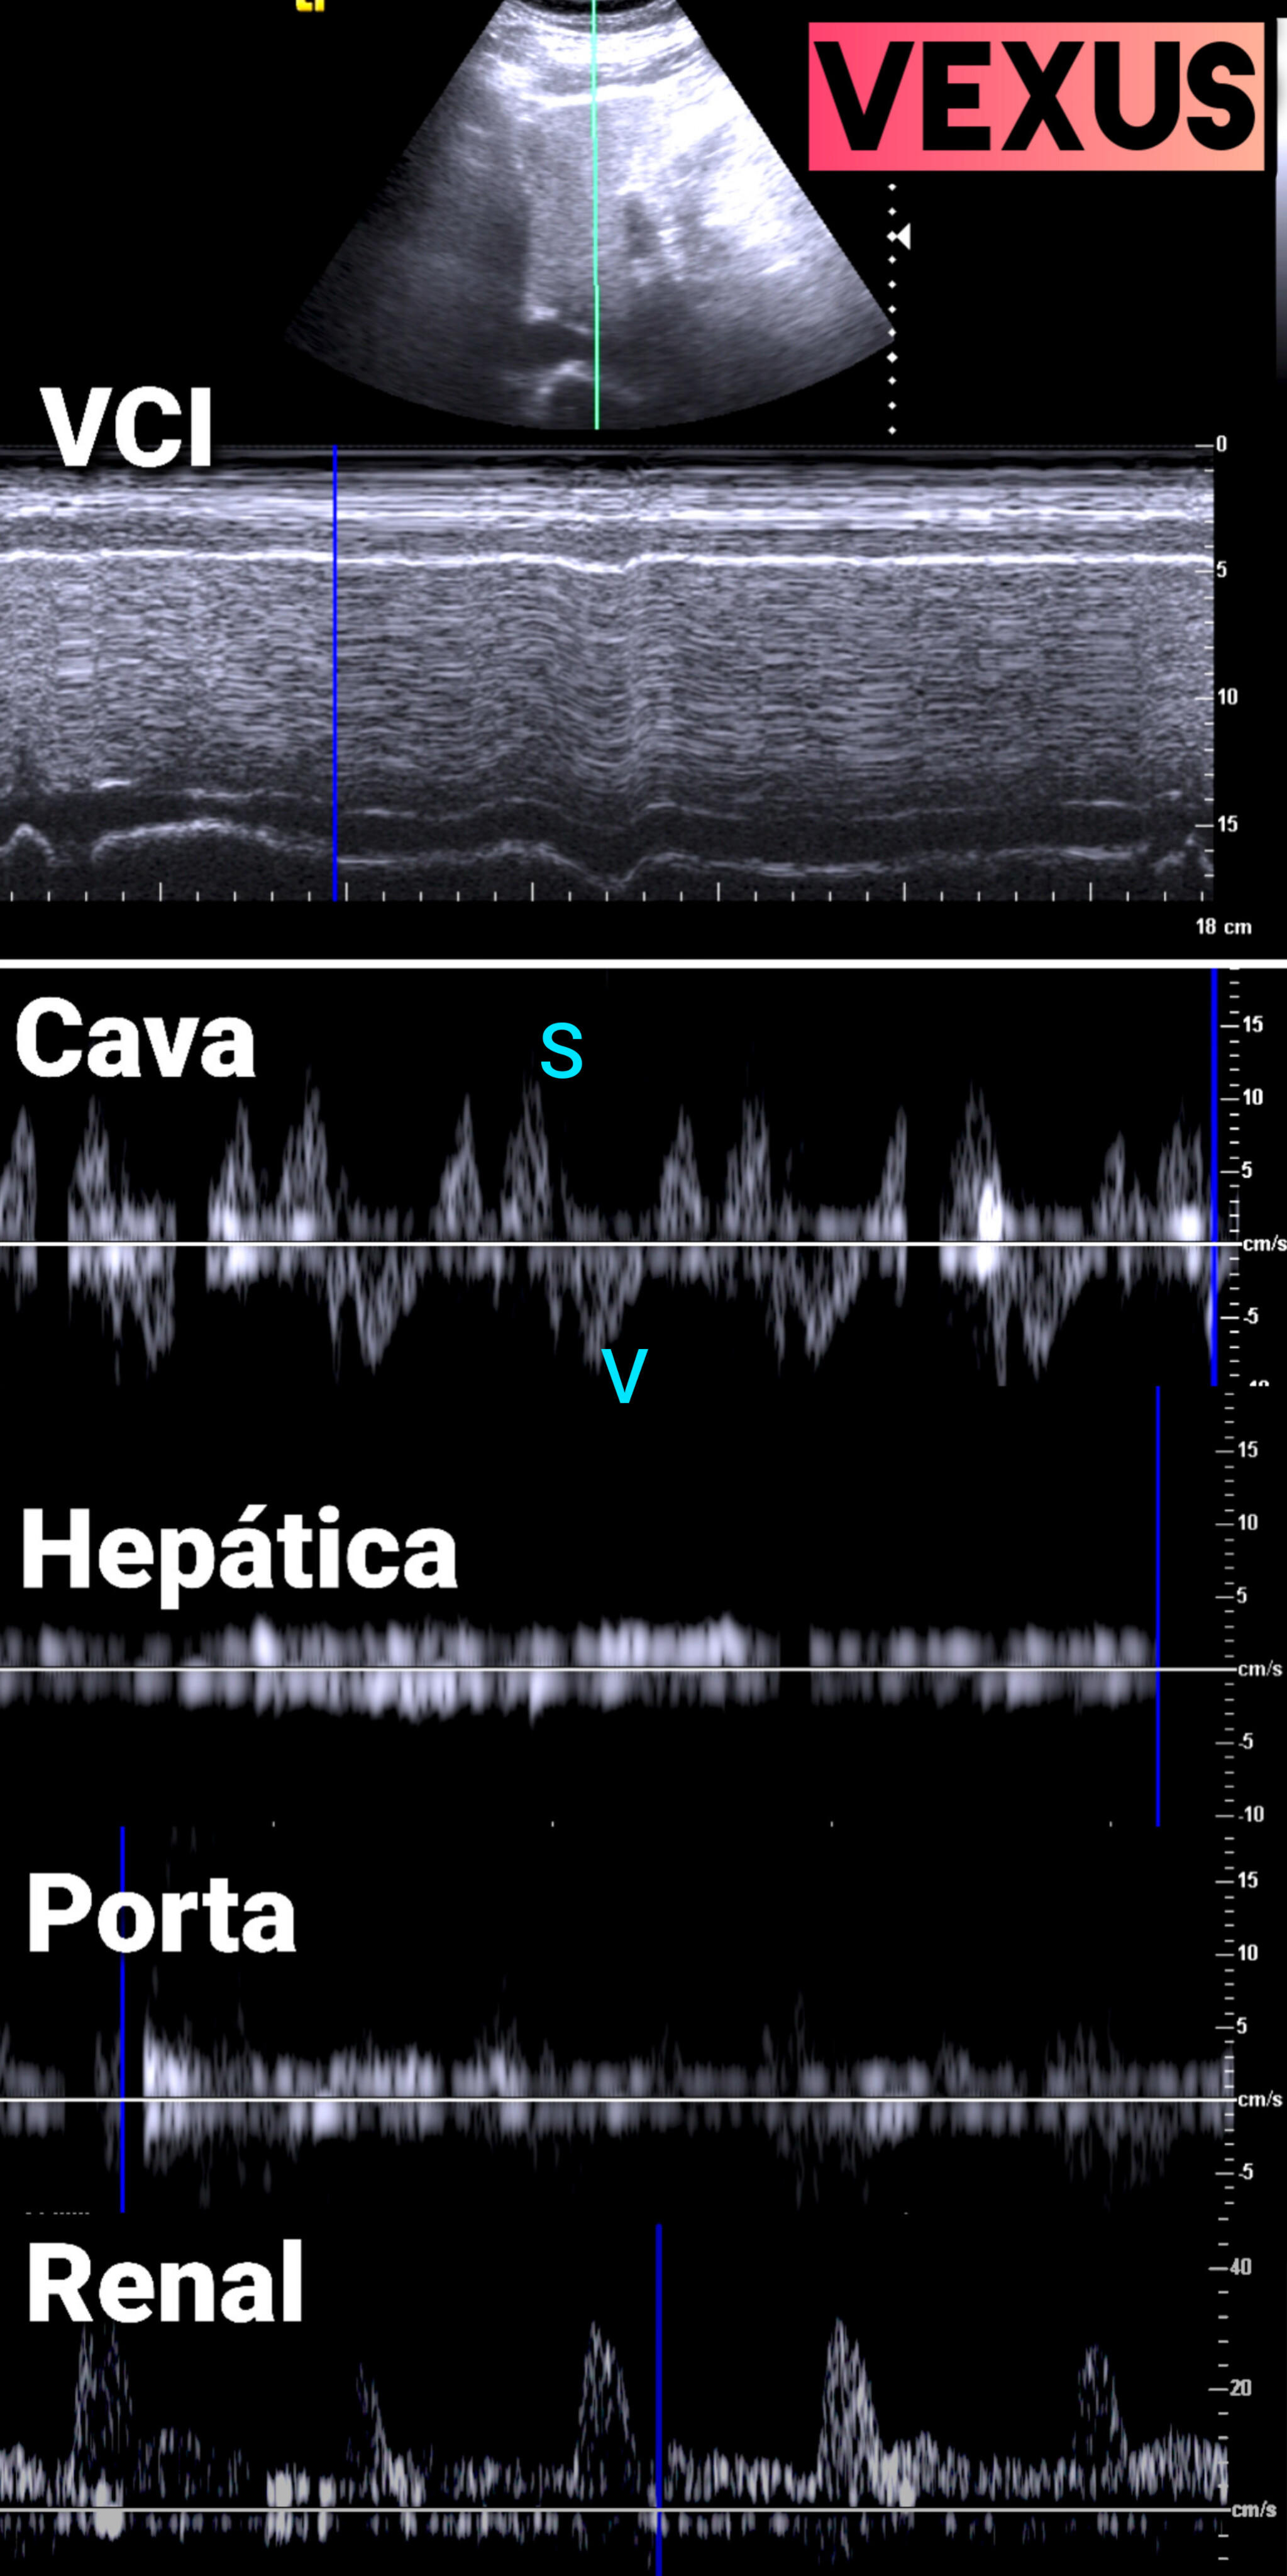

VEXUS: Vena cava inferior VCI 2,1 con colapsabilidad > 50%; Flujo portal y renal continuo.

Desde Medicina de Familia, debemos ser proactivos en la detección y control de la IC y sus factores predisponentes. La ecocardioscopia y VEXUS en consulta complementa a ECG, Radiografía y analítica con ProBNP y CEA125. Finalmente, la longitudinalidad en Medicina de Familia nos permite tener presente los antecedentes personales así como los familiares.